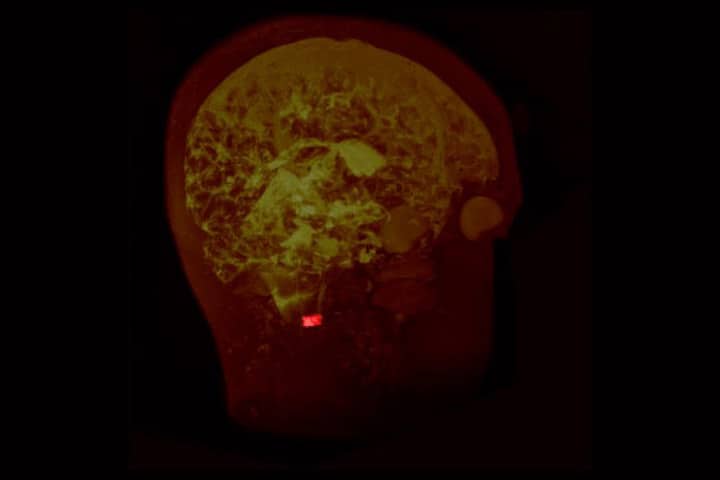

Les 25 et 26 mai, la plateforme de découverte scientifique SPINE invite le grand public à analyser des images IRM pour faire avancer la recherche. Une version de la plateforme à destination du tout public est en phase de test : venez participer à son expérimentation en ligne et découvrez l’imagerie cérébrale dans le cadre d’un projet de sciences citoyennes original sur la sclérose en plaques.

Le projet SPINE

Fruit d’une collaboration internationale entre l’équipe du professeur Charles Guttmann (Brigham and Women’s Hospital, établissement affilié à Harvard Medical School), et l’université de Bordeaux, en particulier le LabEx TRAIL, ainsi que les pôles de Neurologie et de Radiologie du CHU de Bordeaux, SPINE est à l’origine une plateforme utilisée par les médecins chercheurs dans les laboratoires de recherche. Elle leur permet par exemple d’analyser des images IRM pour identifier des zones du cerveau atteintes de lésions et dégénérescences associées à des maladies neurodégénératives. Un travail chronophage pour lequel la plus-value des spécialistes est limitée. Les chercheurs ont eu l’idée d’ouvrir l’accès à la plateforme à des contributeurs non scientifiques, afin qu’ils les aident à analyser les milliers d’images dont ils disposent. Plus les contributeurs seront nombreux et assidus, plus l’analyse sera rapide et plus les chercheurs auront matière à avancer. Une pratique innovante à la frontière entre médiation scientifique et recherche.